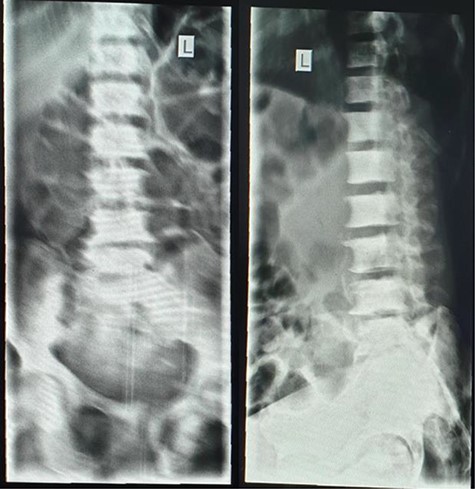

A lumbar sacral X-ray relieved severe osteoblastic changes in the vertebral bodies and the pelvic bones (Fig. 4). On chest X-ray, there were the presence of interstitial changes and increased thoracic cage bone density.